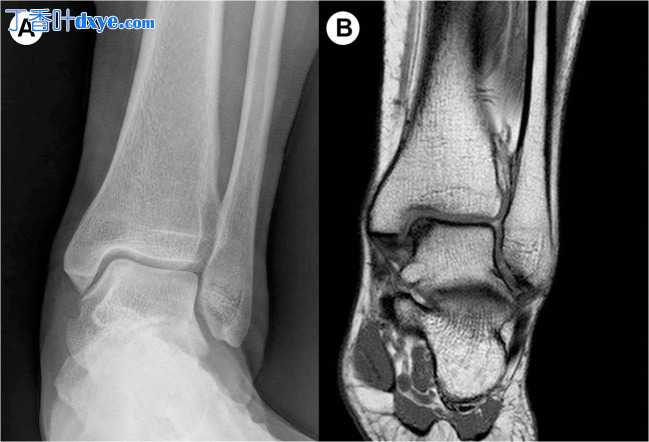

踝关节韧带重建术后 5 个月的患者随访   图 2

(A 和 B)距骨穹窿骨软骨损伤伴有慢性踝关节不稳。